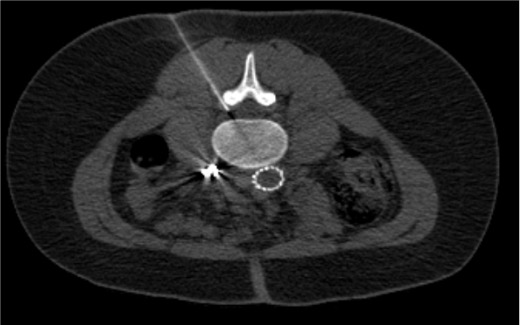

CT guidance — alternative to fluoroscopy for any of the three approaches. Particularly useful in post-surgical anatomy, obese patients, or when precise needle trajectory is needed to avoid spinal hardware.

Advance 22 G or 25 G spinal needle toward the target under oblique guidance; rotate to AP and lateral to confirm depth (needle tip at mid-pedicle depth on lateral).

Transforaminal needle positioned at the "6 o'clock" position of the pedicle (safe triangle) — inferolateral to the pedicle and superior to the exiting nerve root.Transforaminal contrast spread along the exiting nerve root sleeve and into the anterior epidural space — confirms epidural placement prior to non-particulate steroid injection.